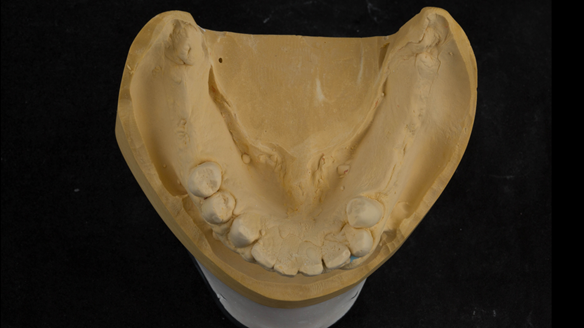

This newsletter describes in step by step detail the transition from acrylic based immediate dentures to metal based definitive dentures.

- Definitive dentures (Mk 2) – complete upper metal reinforced and lower cobalt chromium based partial of hygienic Scandinavian design to be made 9 - 12 months after extractions of all upper teeth and LR5 and LL4

The clinical situation and treatment process is shown in detail below with photographs.